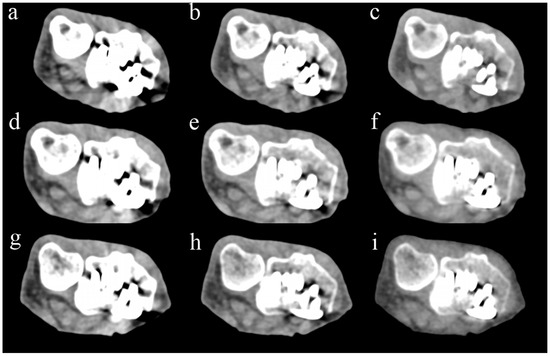

Comparison of STD images (Figure 1) revealed no significant difference in the subjective scores of cortical bone visibility between PCCT and EIDCT (Table 4).

Figure 1. Comparison of photon-counting CT (PCCT) and energy-integrating-detector CT (EIDCT) images in the standard (STD) mode. Images were obtained using (a) Alpha, (b) Drive, (c) X.cite, (d) Force, (e) AS, and (f) Flash scanners. Qualitative scores were made using the image (b) as a reference. Although the appearance of cortical bone and trabecular bone in each image is similar, the PCCT image (a) has less noise than the EIDCT images (bf).

Even in UHR mode, there was no significant difference in the score for the visibility of trabecular bone between PCCT and all EIDCTs, and there was also no significant difference in the visibility of cortical bone with three EIDCTs (Figure 2 and Table 5). In contrast, PCCT had significantly higher scores of image quality than three EIDCTs in STD mode and all EIDCTs in UHR mode.